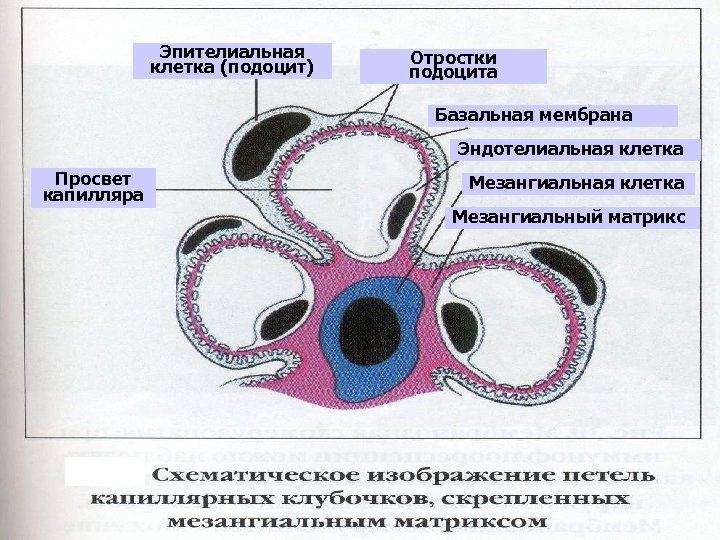

Эпителиальная клетка (подоцит) Отростки подоцита Базальная мембрана Эндотелиальная клетка Просвет капилляра Мезангиальная клетка Мезангиальный матрикс